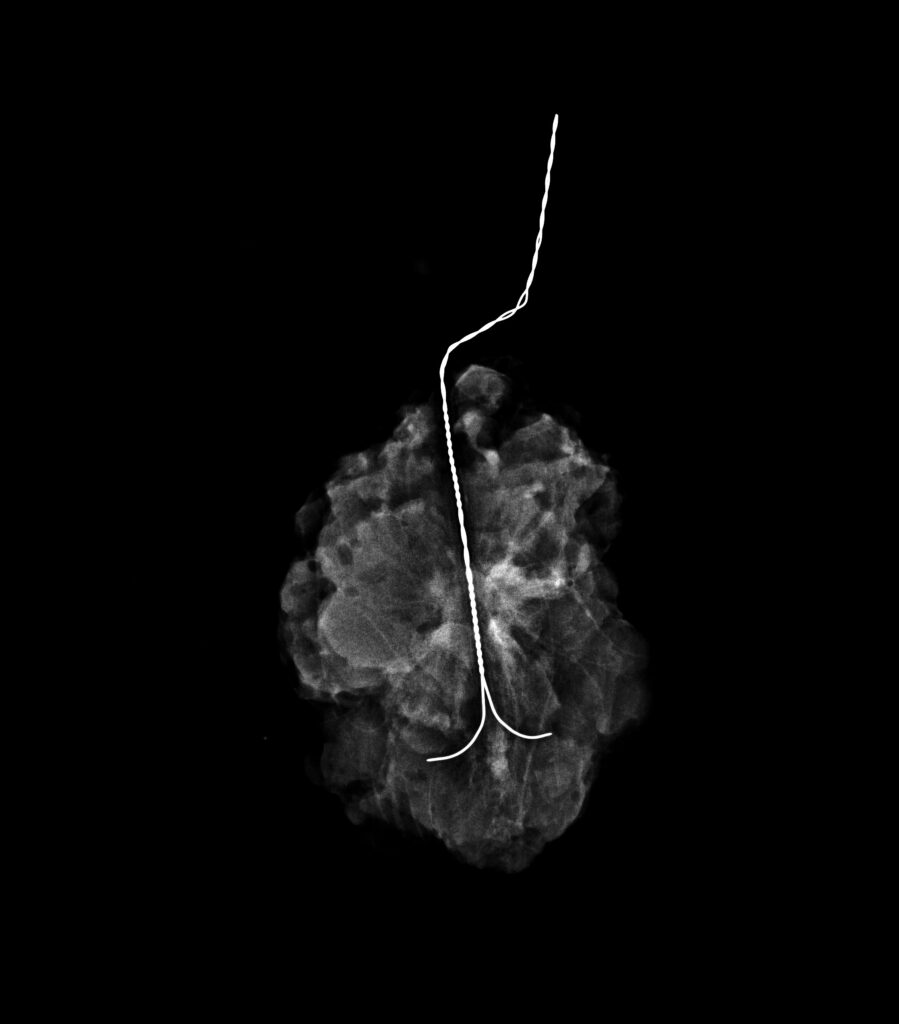

Tipos de estudio mamografico

CATEGORIAS BIRADSv2025